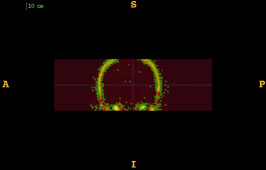

Figure 1 shows the examples of pixel selection masks generated using tested approaches at the highest resolution level for pixel sampling rate 0.5%. It is obvious that the samples generated with the URS approach are extremely spread, whereas the samples generated with the GMS approach are overly concentrated along the gradient magnitude structures present in the image. The proposed approach produces samples that balance those two extremities.